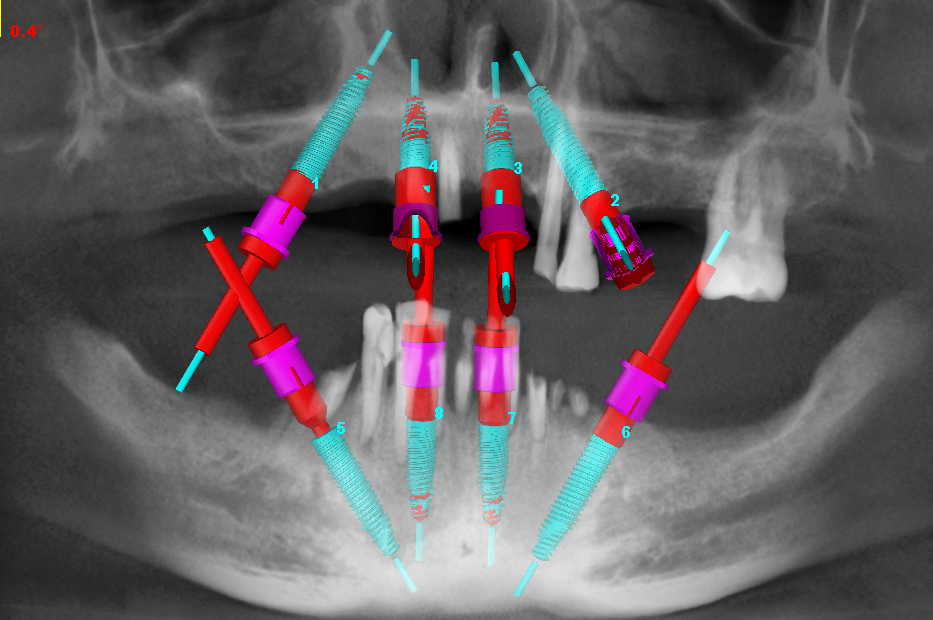

All on 6 – Straumann BLTЛікаріAll on 6 – Straumann BLTПроблема

Хронічний генералізований пародонтит, тотальний страх стоматологів

РішенняВидалення всіх зубів, встановлення 12-ти імплантатів Straumann BLT та тимчасове протезування металоакриловими протезами

Термін лікування5 днів